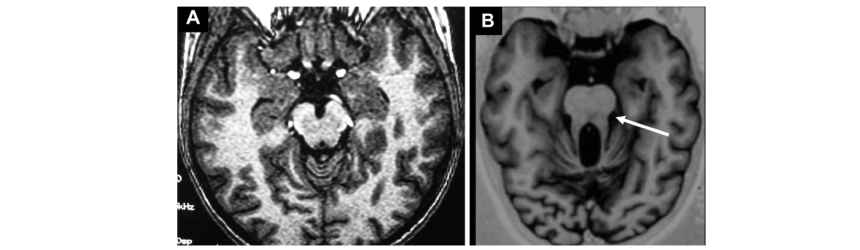

Diagnosticul în Sindrom Joubert poate fi sugerat de modificările respiratorii, dar malformația cerebrală se confirma prin CT și în special RMN cerebral.

- Veți auzi doctorul vorbind despre o imagine RMN specifică în această afecțiune numită “semnul măseluței”. În Sindrom Joubert, în afara unei absențe parțiale sau complete a vermisului cerebelos (partea anatomică a creierului mic responsabilă de echilibru și coordonare și care face legătura între cele două părți ale acestuia numite emisfere cerebeloase) există o lipsă de dezvoltare a peduncului cerebral, parte a trunchiului cerebral, formațiune aflată în apropierea cerebelului și o formă specifică a ventriculului patru în aripă de liliac. Pe o anumita secțiune a RMN apare imaginea caracteristică de “măseluță”.